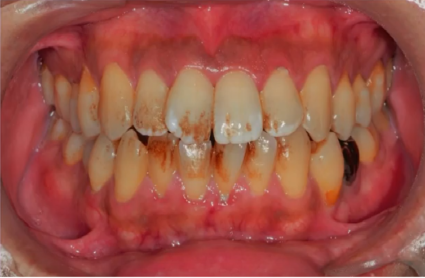

そしてタバコを吸う方で悩んでいる方が多いのがタバコのヤニです。タバコのヤニが歯に着くと・・茶色くなって見た目が悪いですよね。また見た目の問題だけではなくて、ヤニのせいで歯がザラザラしてばい菌が張り付きやすくなってしまったり、いつまでも口の中や歯茎にニコチンなどの有害物質が染み出しつづけるようになってしまいます。口臭の原因にのなりますね。

タバコのヤニは落とせる?

タバコのヤニは頑固に歯にこびりついているので、頑張って歯を磨いてもなかなか取れないところもあるでしょう。そこで歯医者さんに行って歯のクリーニングをしてもらおう!!と思い歯科医院に来院される方は多いですが、注意が必要です。

当院でも多くの患者さんが歯のクリーニングをしに来院していますが、ほとんどが「歯周病・虫歯の予防としての処置」として行っている歯石除去です。健康保険を使う場合は決まりで検査をして、歯周病や歯肉炎ですよ・・という診断結果必要になるのです。なので歯周ポケットをはかったり、レントゲンを撮ったり、口の中の写真を撮ったりして検査が必要になるのです。ですので、タバコのヤニを取りたい!!と思っても、保険の決まりで病気に対する処置しかできないので(タバコのヤニは病気ではないので・・)クリーニングをうけることは可能ですが、ひどくこびりついたヤニは落とせない可能性が高いです・・。

では、ヤニをどうしても落としたい!!というときは、保険を使わずに歯のクリーニングを受けましょう。そうすれば保険のルールに縛られることはないので、タバコのヤニだって綺麗に落としてもらえます。ただし、健康保険適用ではないので、費用は少し高くなります。でも保険を使って検査・クリーニングに何回も通う(歯石が沢山ついていたりすると1回ではクリーニングは終わらないことが多いです)と費用もそれなりにかかるので、自費でクリーニングをした方が、ヤニもキレイになるし、歯周病の予防にだってなるので、もしかしたら保険よりも自費の方が安くすむケースもあるのです。何回も歯医者さんい通わないといけない・・・というめんどくさがりの方にも最適なのではないでしょうか??